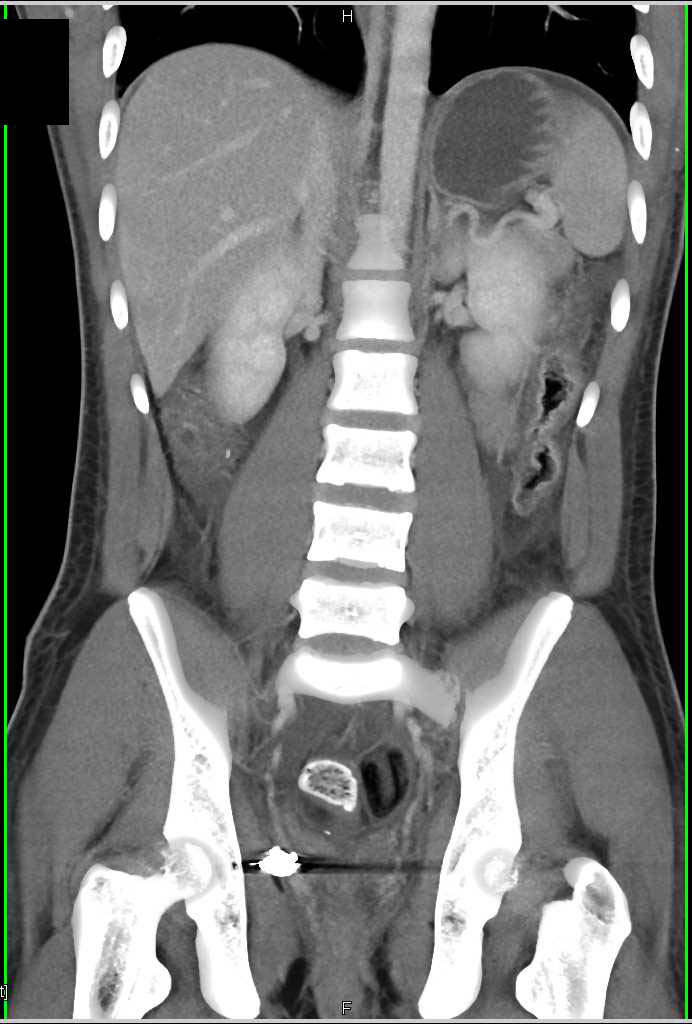

Diagnosis

3D Rendering of Complex Elbow Fracture and Dislocation